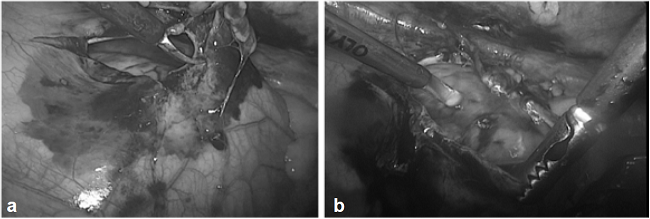

En 1997, Morales, et al., reportaron una serie de 108 pacientes con trauma precordial penetrante, estables, estudiados con una ventana pericárdica realizada por toracoscopia; en 31 % de ellos se identificó hemopericardio traumático. Todos recibieron tratamiento quirúrgico abierto y ninguno presentó complicaciones secundarias al procedimiento 7. Desde entonces, la ventana pericárdica por toracoscopia se ha incorporado al arsenal disponible para estudiar este grupo de pacientes.

A la fecha, se ha reportado la posibilidad de practicar ventanas pericárdica transdiafragmáticas por laparoscopia, y existen reportes ocasionales de reparo de lesiones cardiacas con técnicas mínimamente invasivas 6,33,35,36,37 (figura 2).

Se practicó ventana pericárdica mediante técnicas mínimamente invasivas en 56 casos y, ventana pericárdica subxifoidea, en los 59 restantes. La ventana pericárdica fue positiva en 32 individuos, de los cuales 12 fueron manejados con evacuación del pericardio y lavado hasta descartar una hemorragia activa. Las dos terceras partes de los pacientes con ventana positiva abordados con técnicas mínimamente invasiva, fueron manejados sin toracotomía ni esternotomía; solo el 20 % de los explorados con ventana pericárdica subxifoidea fue manejado de esta manera (tabla 5) 41,. La posibilidad de examinar la herida y comprobar por visualización directa la ausencia de sangrado, es responsable de esta diferencia (figuras 3 y 4).